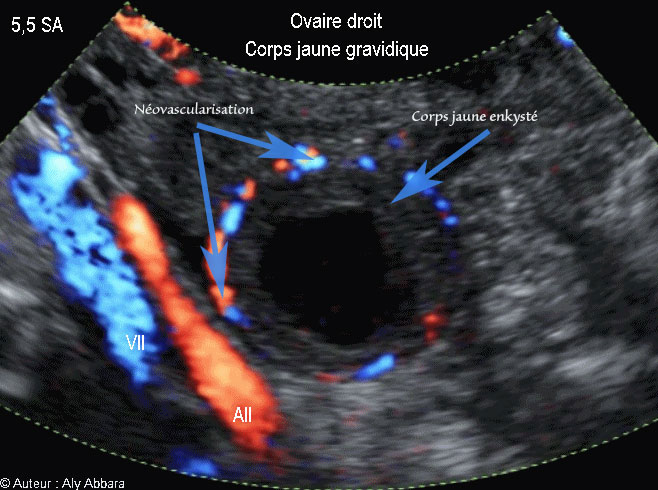

Corps jaune gravidique dans l'ovaire droit - جسم أصفر حملي في المبيض الأيمن -  5,5 SA

Corps jaune gravidique enkysté, de l'ovaire droit - جسم أصفر حملي في المبيض الأيمن -  5,5 SA

• Vidéo et image animée échographiques montrant un corps jaune gravidique, dans l'ovaire, chez une femme enceinte de 5,5 SA :